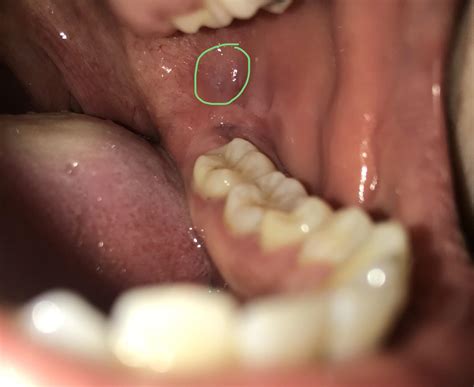

• biting cheek when eating

• cheek bite in adults

• biting inside cheek

• stop cheek biting overnight

• how to stop chewing cheeks

• chewing inside of cheek